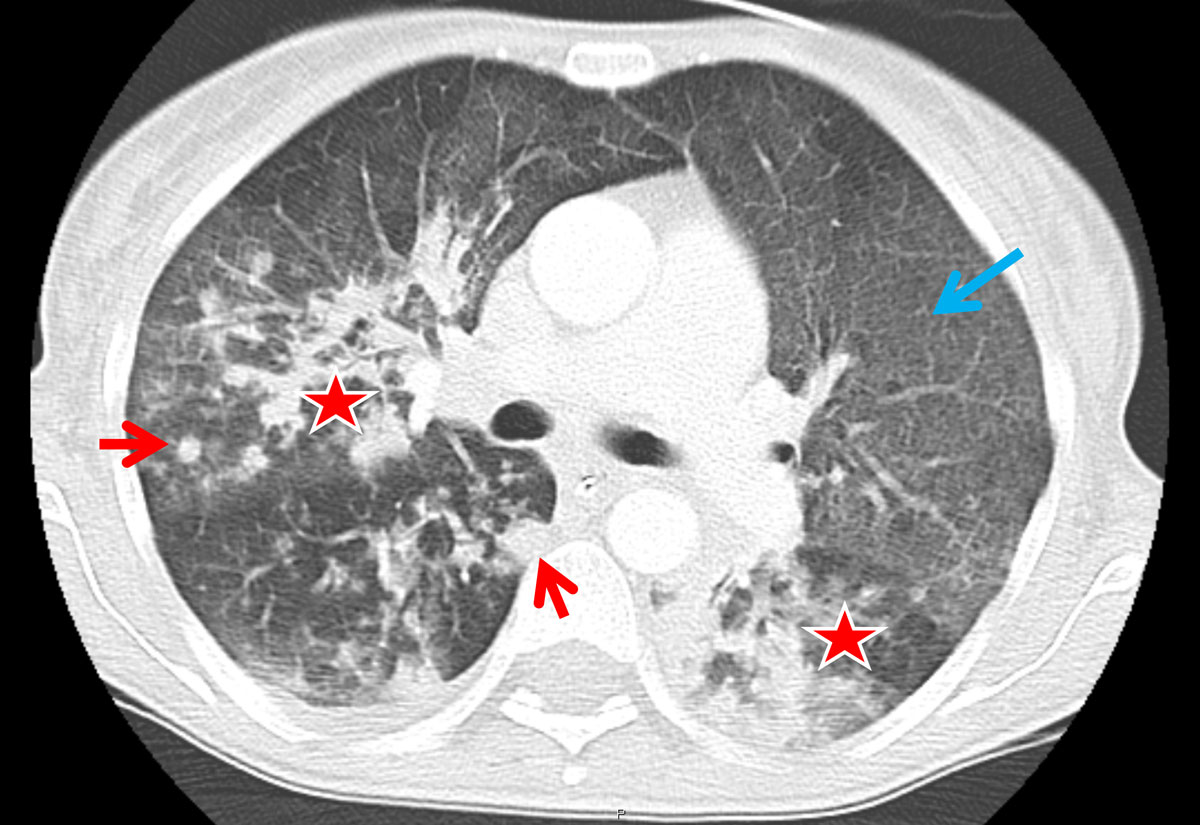

A total of 47 different chest patterns were recorded in the reading sessions, including pleural alterations and lymph node enlargement. As compared with HIV, consolidations and solid nodules (fig. 1) were more frequent in RTRs (91.7 ± 5.6% vs 58.3 ± 6.4% with HIV, p = 0.019 and 91.7 ± 5.6% vs 51.6 ± 6.5% with HIV, p = 0.005, respectively; table 2). All RTRs had ground glass opacifications, whereas none had enlarged hilar lymph nodes.

Figure 1 Axial computed tomography (CT) image from a renal transplant recipient. Typical CT image findings of a renal transplant recipient: patchy consolidations are found in the right upper lobe as well as in the apical segment of the left lower lobe (asterisk). There is also diffuse ground glass opacification present (blue arrow); of note, slight subpleural sparing can be seen in the anterior upper lobes. Solid nodules (red arrows) are also present in the periphery of the right upper and lower lobe.